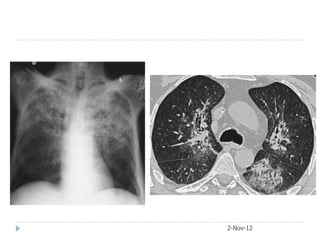

   65-year-old female presented with acute respiratory

failure. She had been sick for two weeks with fever,

confusion, diarrhea, cough, and purulent sputum

production. Her medical checkup two months ago

was unremarkable.

   Urea 11 mmol/L, Creatinine 3.2

   CXR and later CT chest obtained

2-Nov-12

After3 weeks course of macrolide